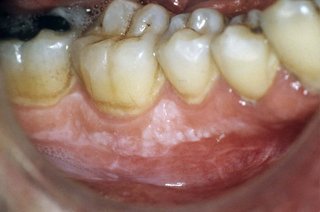

Leukoplakia patches:

- are white patches in the mouth

- are not usually painful

- are an irregular shape

- may be slightly raised

- may have red areas within the patch

- cannot be rubbed or scraped away (patches that can be removed could be oral thrush)